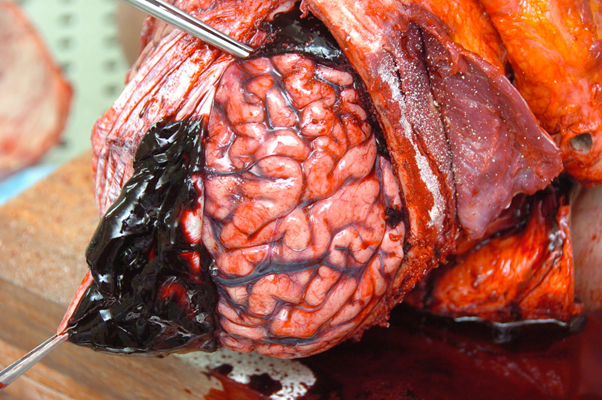

顱內血腫圖片

硬膜下血腫 (50)

硬膜下血腫 (6)